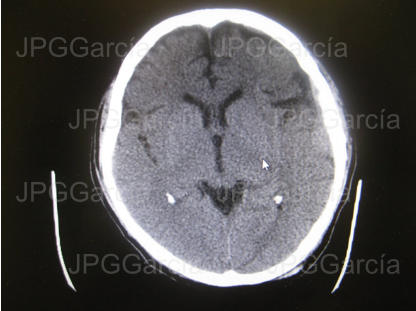

Estudio tomográfico prequirúrgico